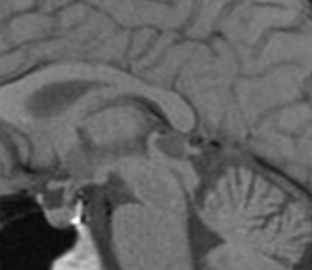

Пинеальная киста расположена в проекции шишковидной железы. Встречается с частотой 4-11%. Размеры обычно не превышают 1 см, но изредка встречаются больших размеров. В таких случаях она вызывает окклюзионную гидроцефалию. При головного мозга она имеет все признаки кисты с примесью белка в жидкости, то есть немного светлая на Т1-взвешенных. Изредка встречается геморрагическое содержимое. Киста может контрастироваться по периферии.

Пинеальная киста расположена в проекции шишковидной железы. Встречается с частотой 4-11%. Размеры обычно не превышают 1 см, но изредка встречаются больших размеров. В таких случаях она вызывает окклюзионную гидроцефалию. При МРТ головного мозга она имеет все признаки кисты с примесью белка в жидкости, то есть немного светлая на Т1-зависимых МРТ. Изредка встречается геморрагическое содержимое. Киста может по усиливаться периферии при МРТ головного мозга с контрастированием.

МРТ головного мозга. Т1-взвешенная сагиттальная МРТ. Пинеальная киста.